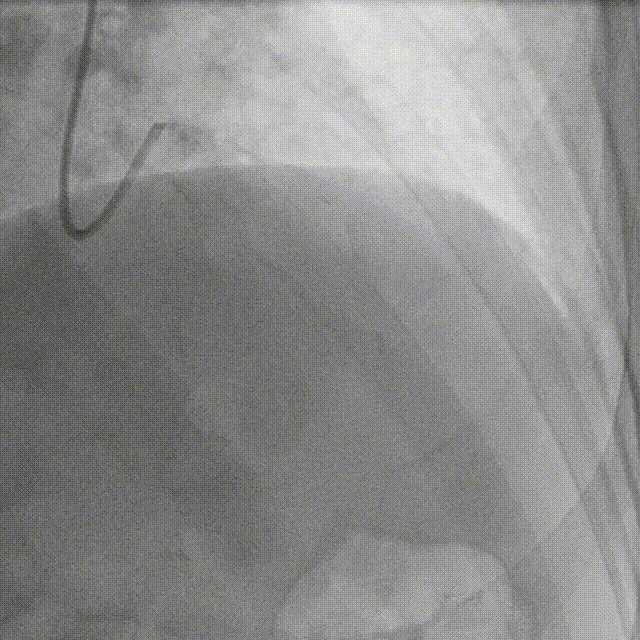

术前冠脉造影:

术前冠脉功能学全面评估:

▶IMR:24;CFR:2.5;FFR:0.76(+)。